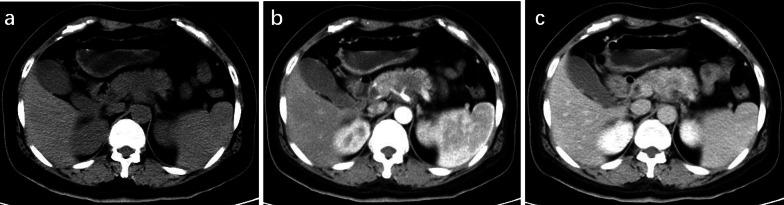

Patients with pancreatic MiNEN more frequently presented with large size and heterogeneous and cystic components compared with PDAC (p < 0.031) and ill-defined irregular margins, progressive enhancement, and adjacent organ involvement compared with NET (p < 0.036). However, vascular invasion was less commonly seen in MiNEN than PDAC (p = 0.010). Moderate enhancement was observed more frequently in MiNEN than in PDAC or NET (p < 0.001). Multivariate logistic analyses demonstrated that moderate enhancement and ill-defined irregular margin were the most valuable features for the prediction of pancreatic MiNEN (p ≤ 0.044). The combination of the two features resulted in a specificity of 93.8%, sensitivity of 83.3%, and accuracy of 91.7%.

We have mainly described the radiological findings of pancreatic MiNEN with ill-defined irregular margin and moderate enhancement compared with PDAC and NET. The combination of imaging features could improve diagnostic efficiency and help in the selection of the correct treatment method.